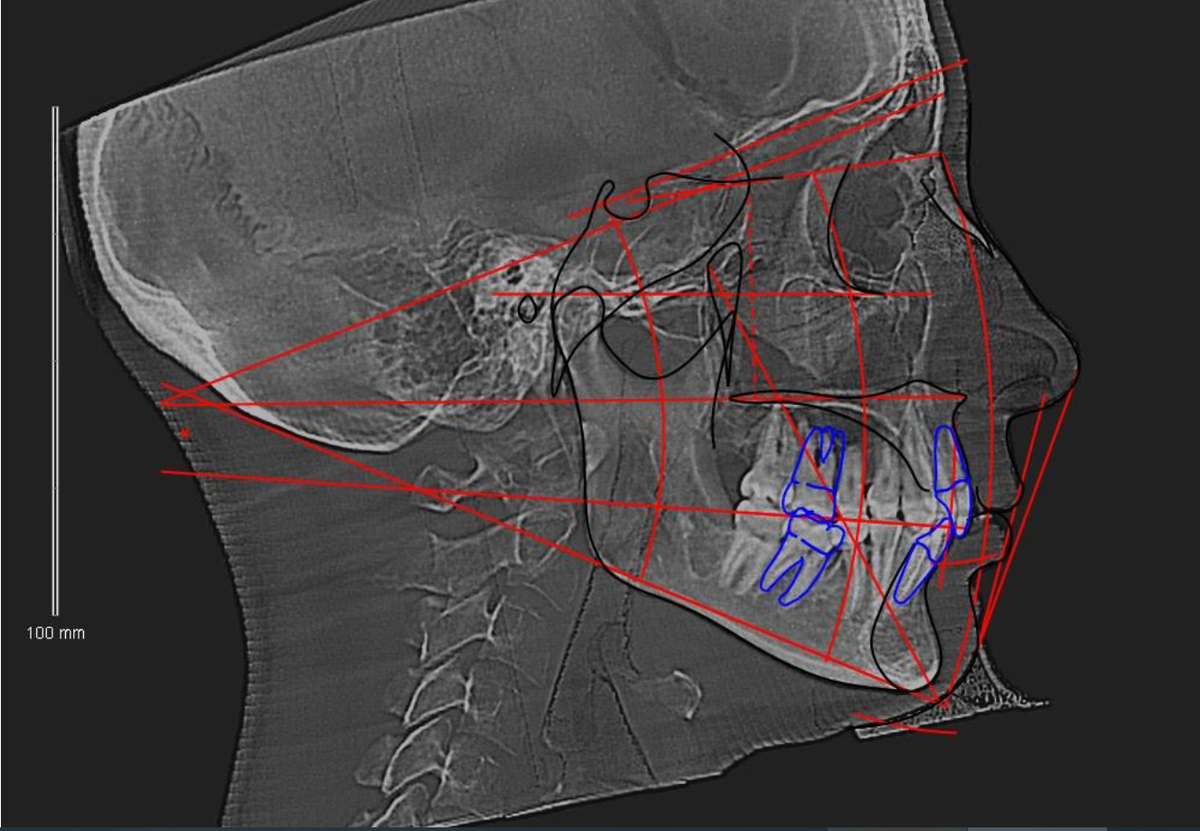

Цефалометрия - это метод анализа черепа на основании рентгенологического снимка. Он позволяет измерить углы и расстояния между ключевыми анатомическими точками, характеризующими рост, форму и взаиморасположение челюстей.

В классической 2D-цефалометрии используется боковой рентгеновский снимок черепа. Однако 3D-цефалометрия, основанная на КЛКТ, значительно расширяет диагностические возможности:

- измерения становятся объёмными, то есть возможен анализ не только по одной проекции, но сразу по трём (сагиттальной, фронтальной и горизонтальной)

- повышается точность локализации анатомических ориентиров, появляется возможность оценивать асимметрию, объёмные деформации, наклоны корней зубов.